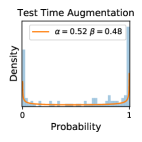

5.1 Distribution of Uncertainty Scores

Distribution of Uncertainty Scores Across Different Severity Levels As explained in Section 3, each uncertainty metric essentially defines an order/ranking among the data points. We conducted an analysis to better understand what data will be assigned high uncertainty under a particular uncertainty metric . Picking out the highest ranked data points (), we calculated the ratio of data points from each SL. Figure 4 summarizes the results as box plots for the Kaggle-DR and the Messidor-2 datasets; additional detailed statistics can be found in Table S.1 in the supplementary materials. From the plot and table, SL1 & SL2 examples account for a higher proportion among the top-ranked uncertain examples across the three ensemble methods. This finding matches our intuition that incipient disease examples (SL1 & SL2) are more likely to be considered uncertain by ensemble methods due to their ambiguity.

Uncertainty Scores on Out-of-Distribution Datasets As an additional experiment, we also tested the performance of the ensemble models on o.o.d. data inputs, which is a classic application of prediction uncertainties [1]. For this task, we produced distribution plots similar to those in Figure 4 for the previous experiment in our supplementary materials. The visualizations for the two o.o.d. image datasets can be found in Figure S.5 for ImageNet and in Figure S.6 for CIFAR-10. The results showed that the majority of o.o.d. data received higher uncertainty scores than in-distribution data for all three ensemble methods, suggesting that these ensemble methods would indeed perform well on o.o.d. detection tasks.

Comparing the three ensemble methods in Figure 4, the stacking ensemble method has the highest ratios of SL1 & SL2 data among the high-uncertainty examples it identified under both mean and var. TTA showed slightly better performance than MC-dropout but still falls behind the stacking ensemble method. Considering the fact that SL0 examples accounted for the majority of the dataset, the stacking ensemble method was much more precise (specific) in selecting truly ambiguous data points that were difficult to classify. From Figure 3, we can also see that the stacking ensemble method greatly outperformed the other two methods in finding false negatives under both mean and var uncertainty metrics.

In contrast, the MC-dropout method showed the worst overall performance among the three, as it can be seen from the high ratios of SL0 examples among the uncertain negatives in Figure 4. The histograms in Figure 2 provides another perspective to look into the phenomenon, where a decent proportion of MC-dropout model’s predictions on SL0 inputs entailed low confidence (far from 0 or 1), which from another angle explained why MC-dropout was less specific in terms of lower FNP; many no-DR inputs (i.e. SL0) were erroneously assigned high uncertainty by MC-dropout models.

It is still an open question why the evaluated MC-dropout networks signaled relatively high uncertainty on SL0 & SL3 & SL4 data that are less likely to be ambiguous. We conjecture that much of the “uncertainty” indicated by disagreement among test-time dropout samples actually reflects the stochastic nature of dropout networks rather than the real decision uncertainty associated with the data. It is worth noting that the MC-dropout model we evaluated was not weak per se; they all achieved above Area Under Curve (AUC) scores on test sets. The weakness of individual test-time samples (which explains their low-confidence predictions on SL0 & SL3 & SL4) might have been hidden when they are aggregated into an ensemble—a well-known advantage of ensemble learning. Our results suggested that the uncertainty information given by implicit ensemble methods such as MC-dropout and TTA might not be as reliable as that from explicit ensemble approaches (e.g., stacking ensembles). Similar findings on MC-dropout can be found in some previous papers [1].